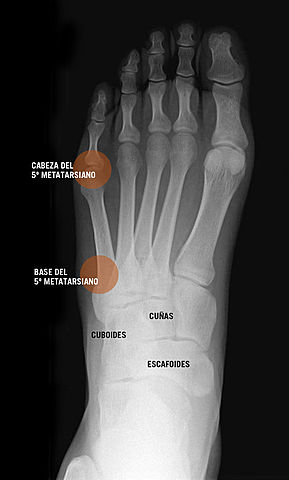

• I broke the fifth metatarsal of the right foot

I broke the fifth metatarsal of the right foot

I broke the fifth metatarsal when I was playing and my right ankle was bent and I spent myself two days walking without knowing that I had it broken with pain